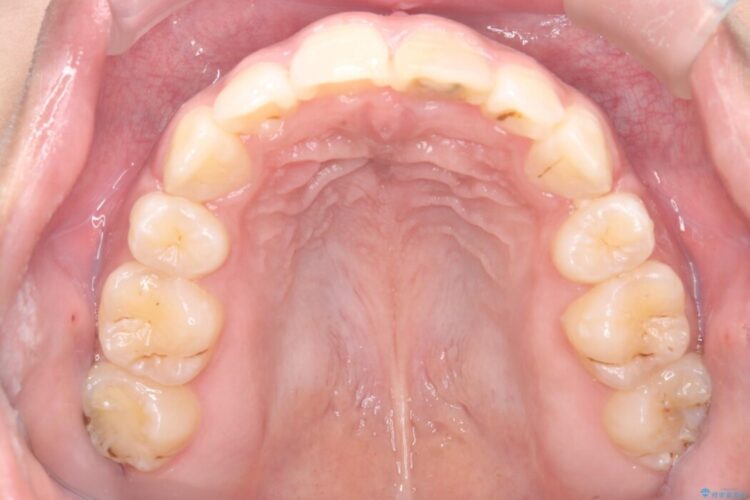

矯正検査の結果、歯列全体のスペースが不足しており、これが突出感の原因となっていました。

無理に歯を並べても口元の突出感は解消されないため、上下左右4番を抜歯しスペースを確保、目立ちにくい審美ワイヤー装置にて治療を行うこととしました。

抜歯によって得たスペースを活用し、審美ワイヤーによる繊細な角度調整を行いながら前歯を後方へ移動。

突出していた口元のボリュームを段階的に抑制し、理想的なバランスへと導きました。